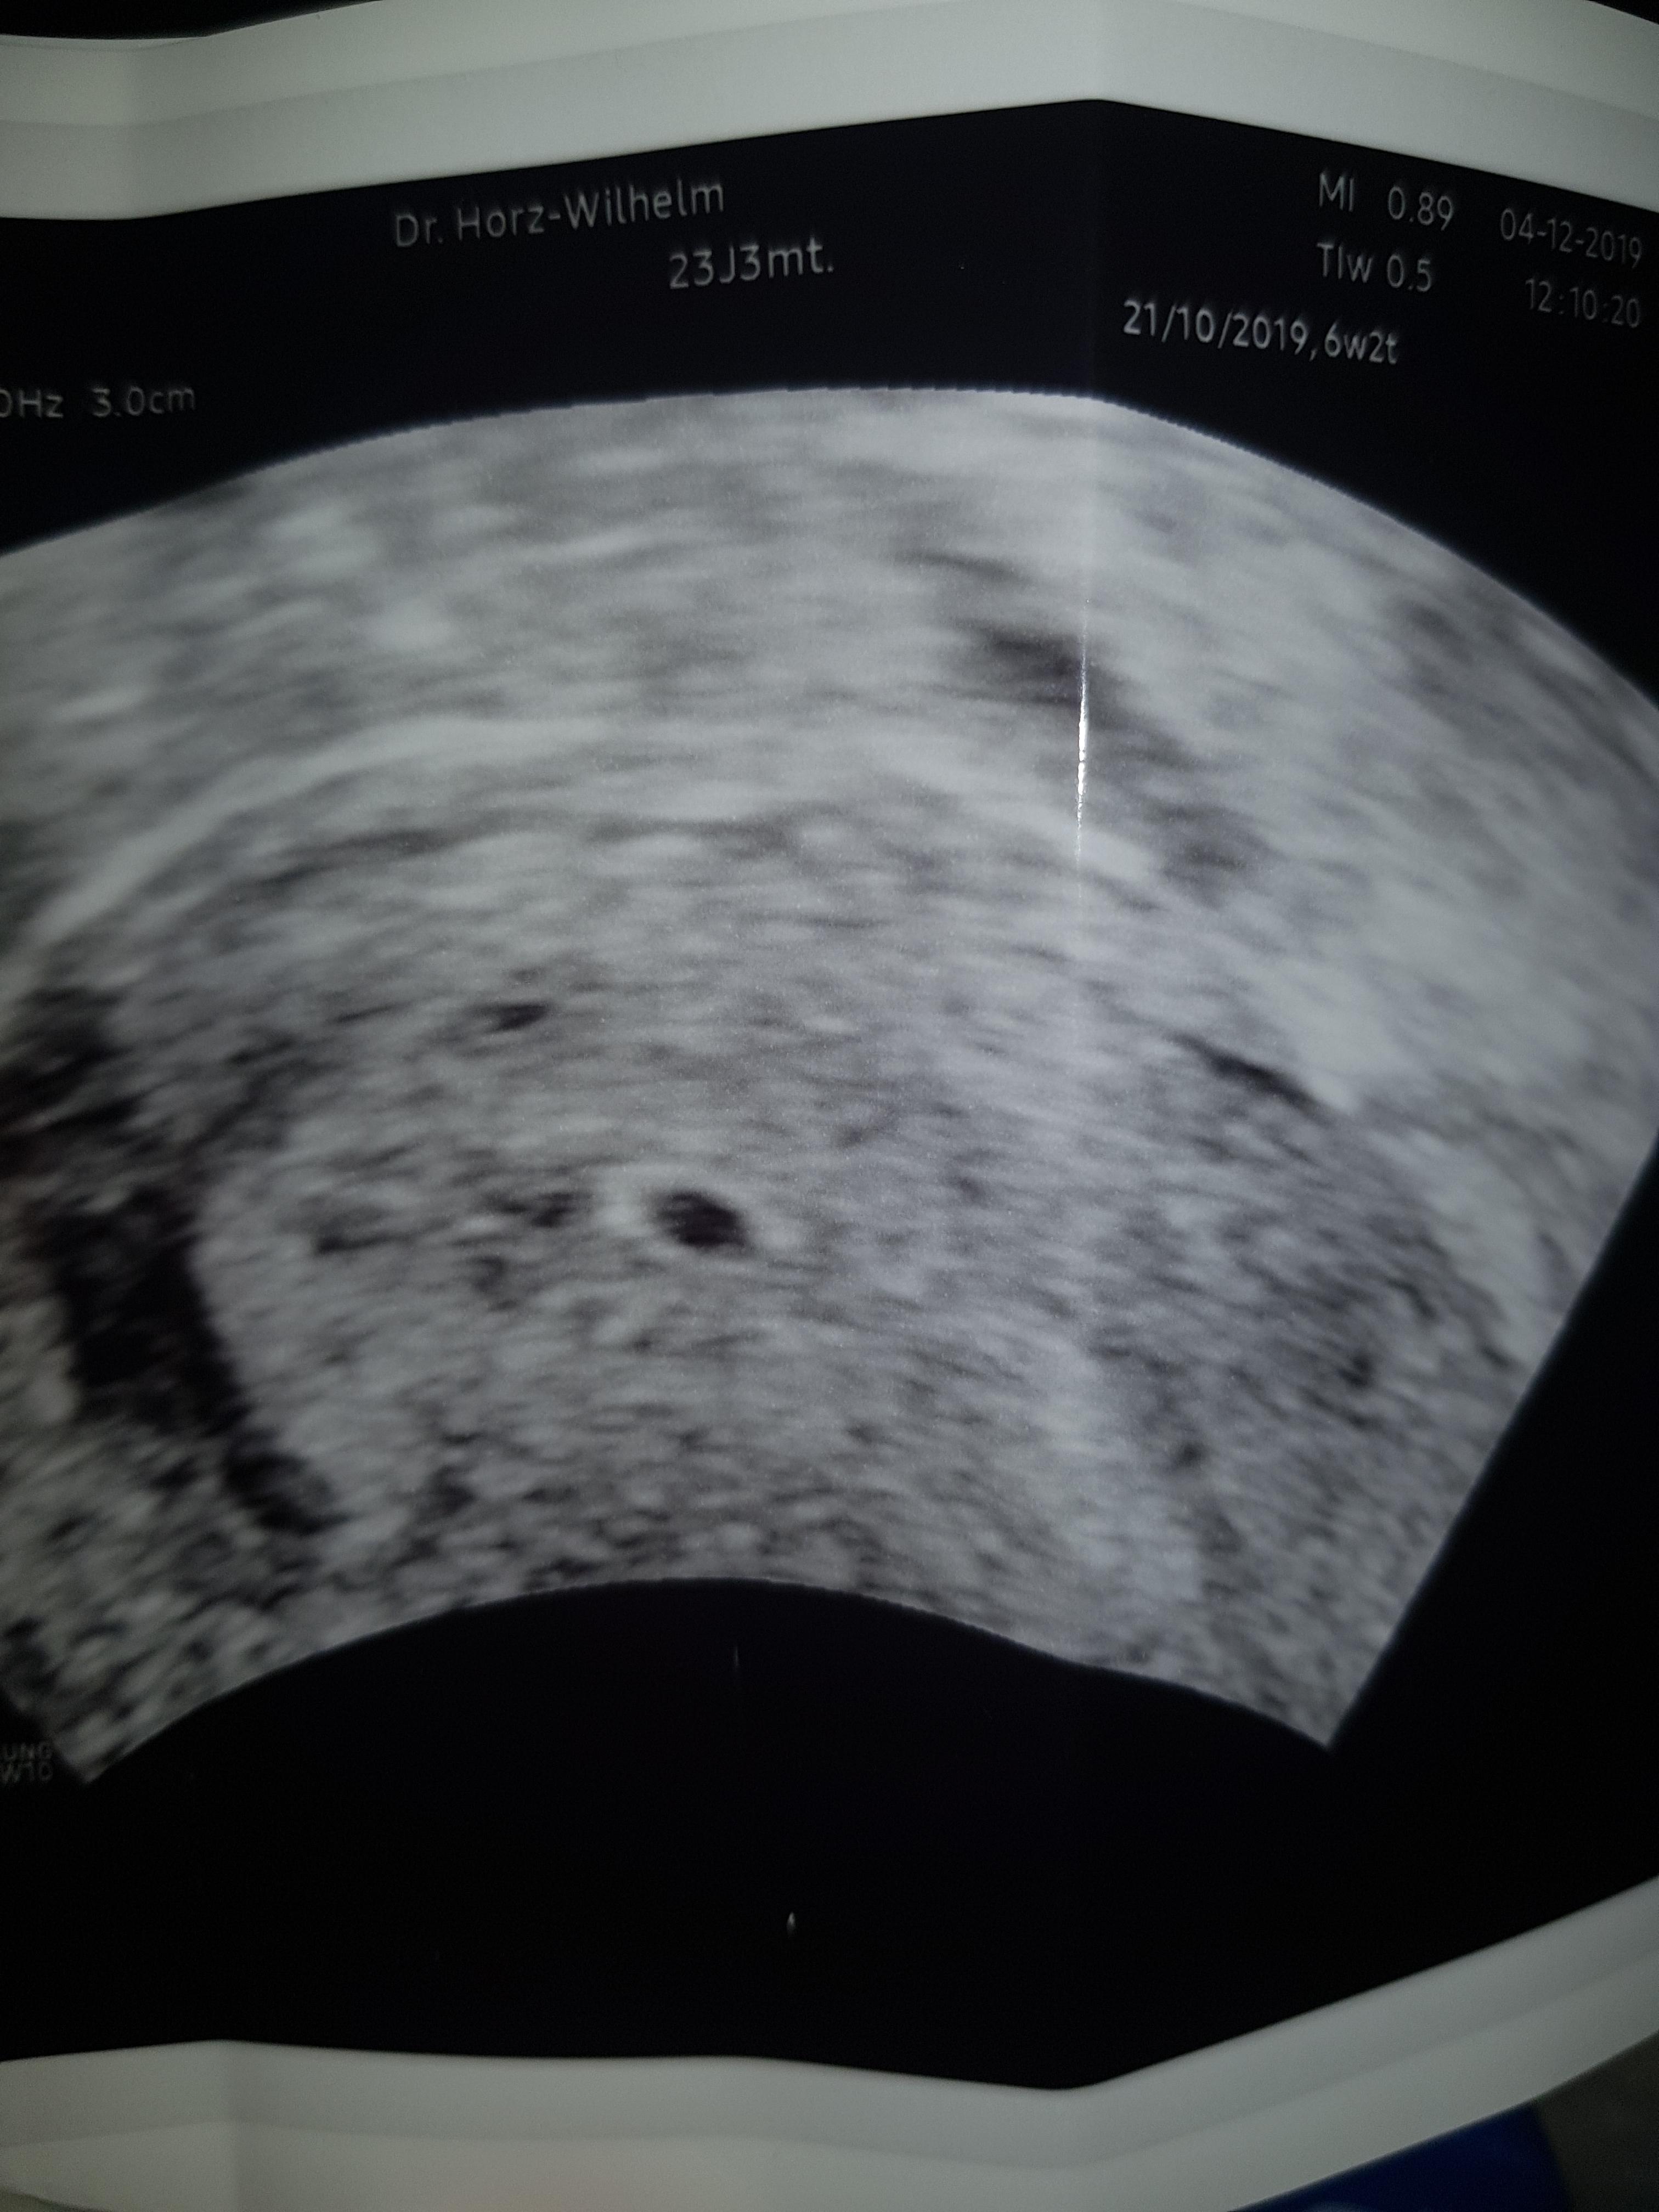

Das Baby in der 10 SSW Auf dem Ultraschallbild ist jetzt bereits ein kleiner Mensch zu sehen Dabei ist der Kopf des Kindes am weitesten entwickelt, da das Baby "von oben nach unten" wächst Die kritischen Phasen der Entwicklung von Herz und Gehirn sind abgeschlossen, auch alle anderen Organe sind angelegt und entwickeln sich in den nächsten Monaten zu ihrer vollen Funktionsfähigkeit und. Hallo, in der 10 SSW ist auf dem Ultraschall ja schon einiges zu sehen oder?. Bei Jungen wird der Penis sichtbar, eine eindeutige Geschlechtsbestimmung durch Ultraschall ist jedoch erst in einigen Wochen möglich In der 11 SSW wachsen außerdem die Därme, die zunächst bis in die Nabelschnur reichen können, um in den kommenden ein bis zwei Wochen dann an ihre richtige Position zu gelangen.

10 SSW Ultraschall Das ist zu sehen Der Fötus (10 Woche) ist jetzt 25 bis 32 Millimeter lang, das entspricht ungefähr der Größe einer Himbeere Lippen und Nase sind klar erkennbar Augen und Ohren haben schon fast ihre endgültige Form Die Füße sind im Vergleich zu den Händen in der 10 SSW noch nicht sehr ausgeprägt. Bei Jungen wird der Penis sichtbar, eine eindeutige Geschlechtsbestimmung durch Ultraschall ist jedoch erst in einigen Wochen möglich In der 11 SSW wachsen außerdem die Därme, die zunächst bis in die Nabelschnur reichen können, um in den kommenden ein bis zwei Wochen dann an ihre richtige Position zu gelangen. Laut Schwangerschaftsrechner bin ich in der 3SSW Habe einen aufgeblähten bauch, ziehen im unterleib, einen echt unrihigen bauch, und bin teilweise ziemlich träge Übelkeit hatte ich bis jetzt nur an 2 tagen All dies sind ja Schwangerschaftssymptome Ist ein aufgeblähter bauch auch ein anzeichen, bereits nach der 3woche?.

In der 10 SSW sind im Ultraschall schon die menschlichen Züge des Babys zu erkennen, weshalb es in diesem Stadium nicht mehr als Embryo gilt Was genau Sie in der 10 SSW auf dem Ultraschallbild sehen können, erfahren Sie in diesem Artikel. 11 SSW Ultraschall Deines Babys In der 11 SSW ist der Fötus 34 bis 41 Millimeter groß Das kindliche Herz ist nun von seiner anfänglichen Platzierung im Kopfbereich in die Brust gerückt Auch die einst transparente Haut Deines Babys wird dicker und vielschichtiger und unter der Oberfläche entstehen Haarfollikel. Vielen Dank für Ihre Antwort Können Sie mir erklären, warum es möglich wäre schon bei 43 eine so gross Fruchthöhle zu haben im Eileiter, dies jedoch ohne Schmerzen?.